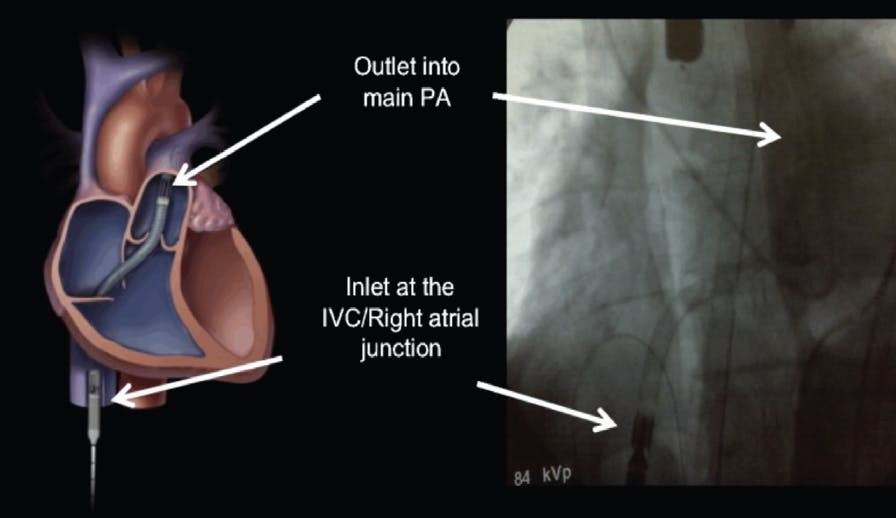

The ProtekDuo is a 29- or 31-F dual-lumen catheter placed via the internal jugular vein into the pulmonary artery. The inflow cannula in the right atrium removes blood from the body, where an external pump then ejects the blood through the outflow lumen to the pulmonary artery. Because the pump is external to the body, an oxygenator can be easily added before blood is returned to the pulmonary artery. Similar to the Impella RP device, use seems to be best in patients with residual RV failure after there has been clot reduction in the pulmonary arteries. Small case series have been published but large-scale studies in PE have not been performed.23 Figure 5 illustrates the ProtekDuo system.

Figure 5. Example of a ProtekDuo device placed via the right internal jugular vein into the pulmonary artery.